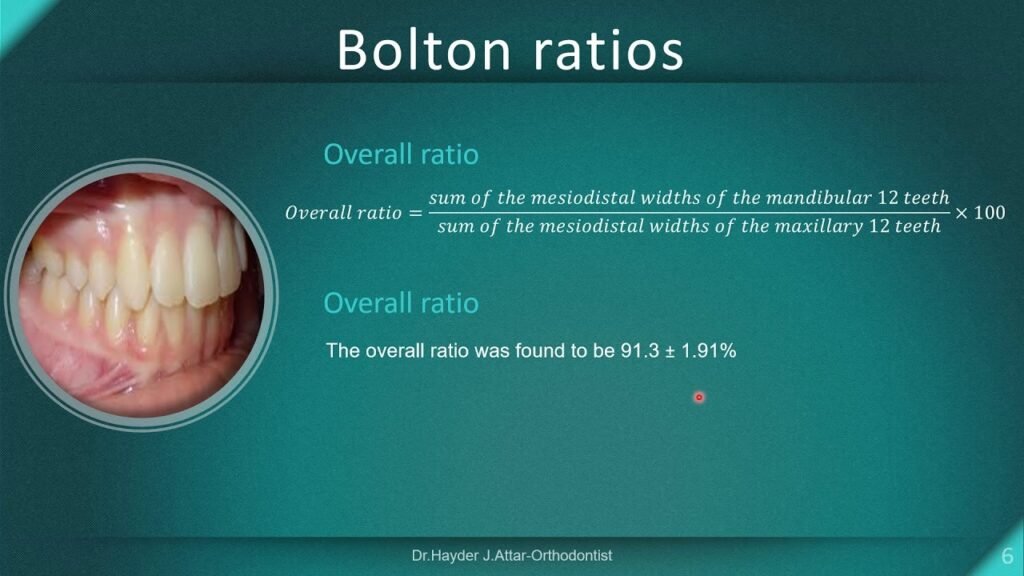

- Space Analysis

- Diastema Characterization

- Width measurement (mm)

- Tooth size analysis (Bolton analysis)

- Black triangle risk assessment

- Root proximity evaluation